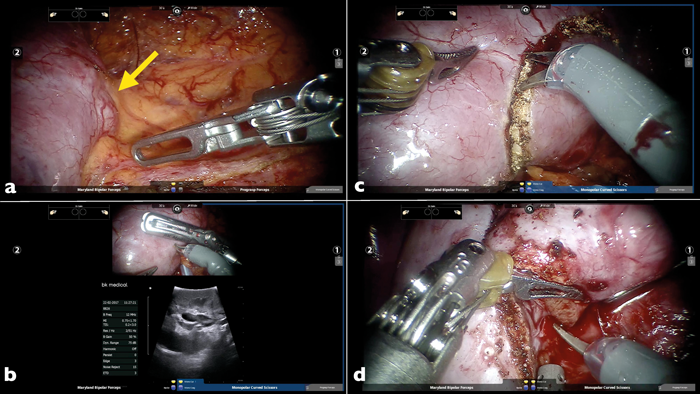

Figure 1: a) Sagittal and b) Axial CT scan to show a small posterior renal tumour (yellow arrows).

Tumours are assessed with preoperative imaging. Modern computed tomography (CT) (Figure 1) and magnetic Resonance Imaging (MRI) scanners provide an excellent amount of detail allowing for accurate assessment of tumour location, size and metastases where applicable. These are key parameters used in the assessment of the tumours. Two scoring systems have been devised to assess tumours; the radius, endophytic / exophytic, nearness to collecting sinus anterior / posterior, location relative to polar lines (RENAL) nephrometry score and PADUA score.